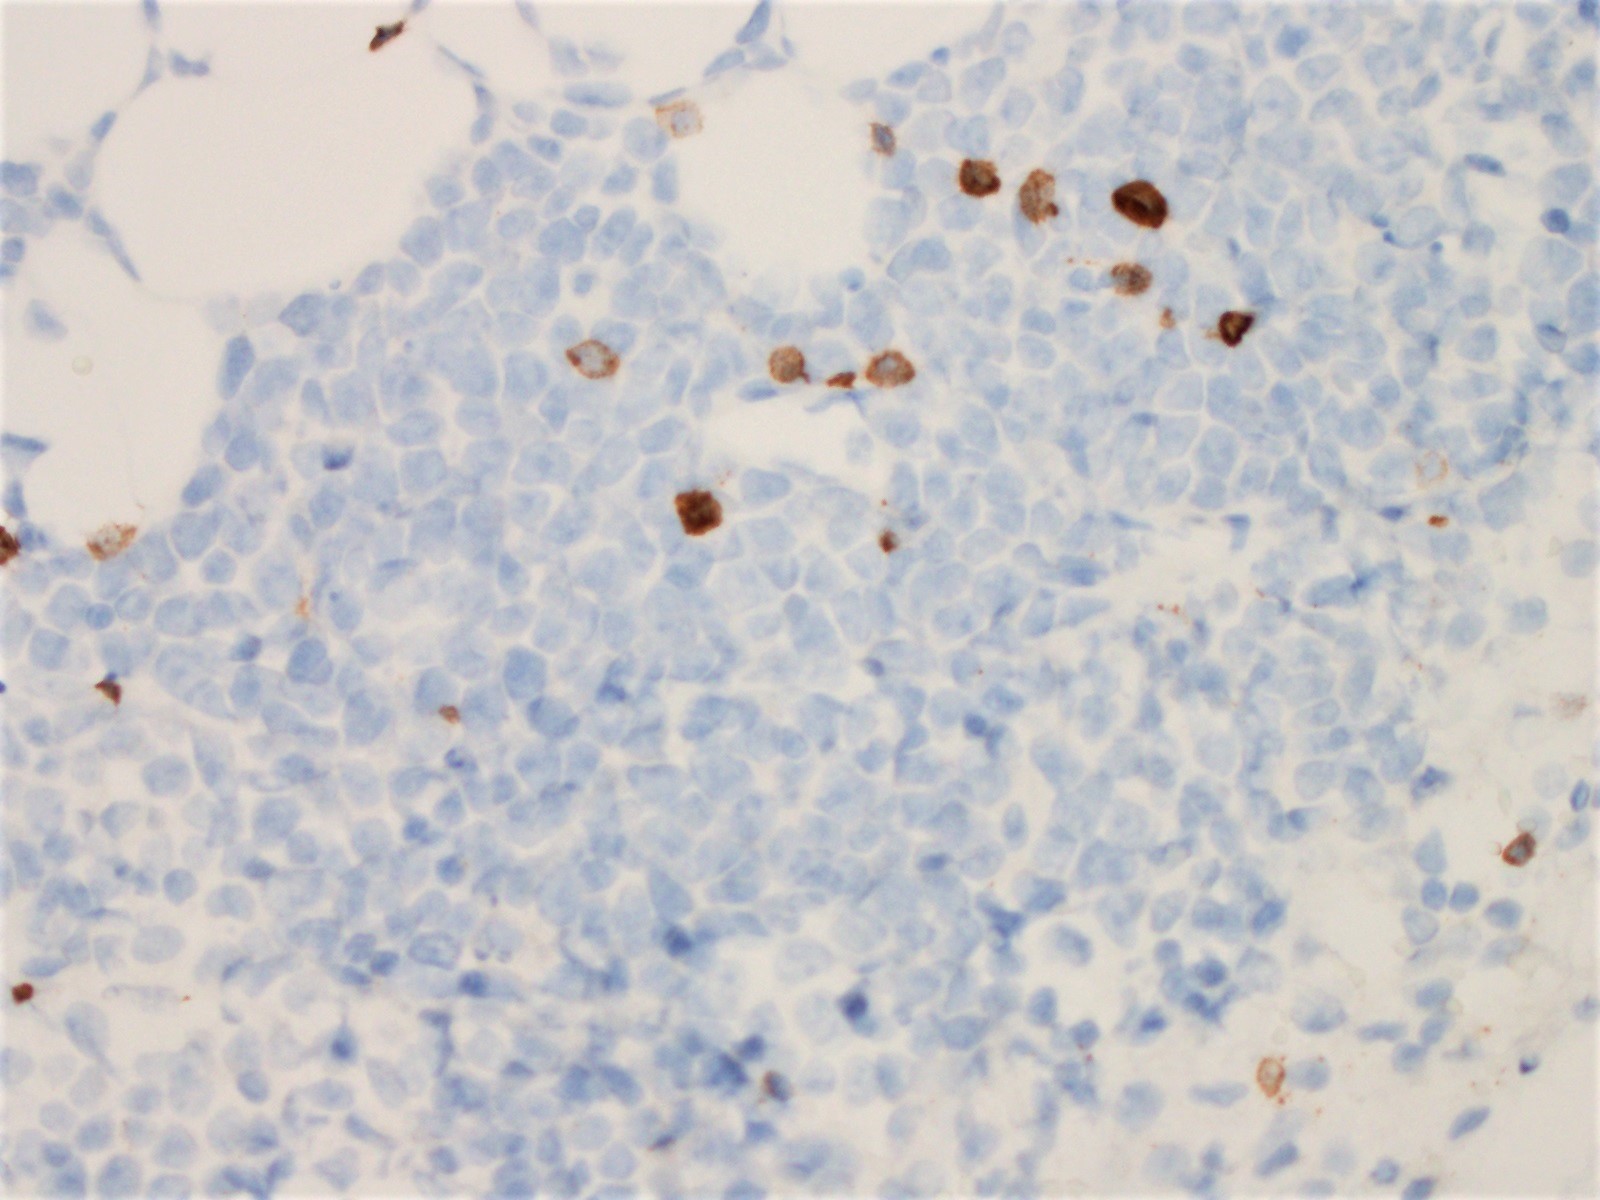

Microscopic (histologic) images

Positive stains

Negative stains

- CD200

- LEF1